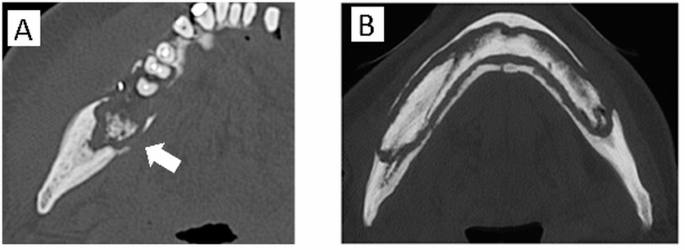

Sequestrum separation (Fig. 2).

Defined as ≥ 90% separation of the sequestrum:

(−): No sequestrum separation.

(+): Sequestrum separation observed.